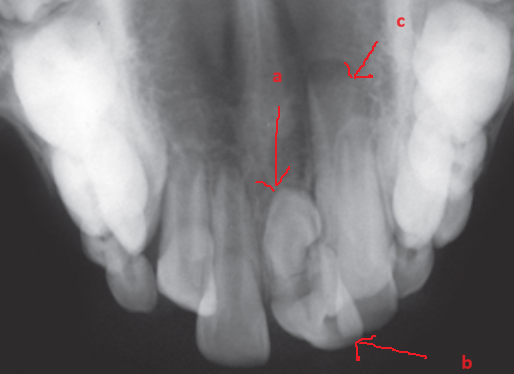

R21 chưa mọc, R11 đã mọc (a), Răng thừa (b), R22 (c) (b)Răng thừa thứ nhất, (a) răng thừa thứ 2, (c) R21 ngầm chưa mọc Phẫu thuật lật vạt:(a) răng thừa thứ 1, (b) R21 ngầm, (c) R22

image 20231218155055 19 502x340

Răng thừa thứ 1đã được nhổ Bộc lộ răng thừa thứ 2 Hình ảnh 2 răng thừa

Hình ảnh sau phẫu thuật 6 tháng, R21 đã mọc lên sau khi loại bỏ 2 răng thừa

Hình 4: Minh họa cho phẫu thuật lấy răng thừa đơn thuần ở một bé trai 9 tuổi